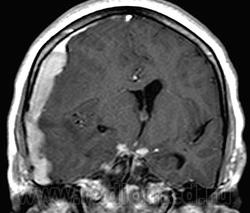

ГМ. СМ. Нейросаркоидоз. Саркоидоз на спинальном уровне. +

Нейросаркоидоз